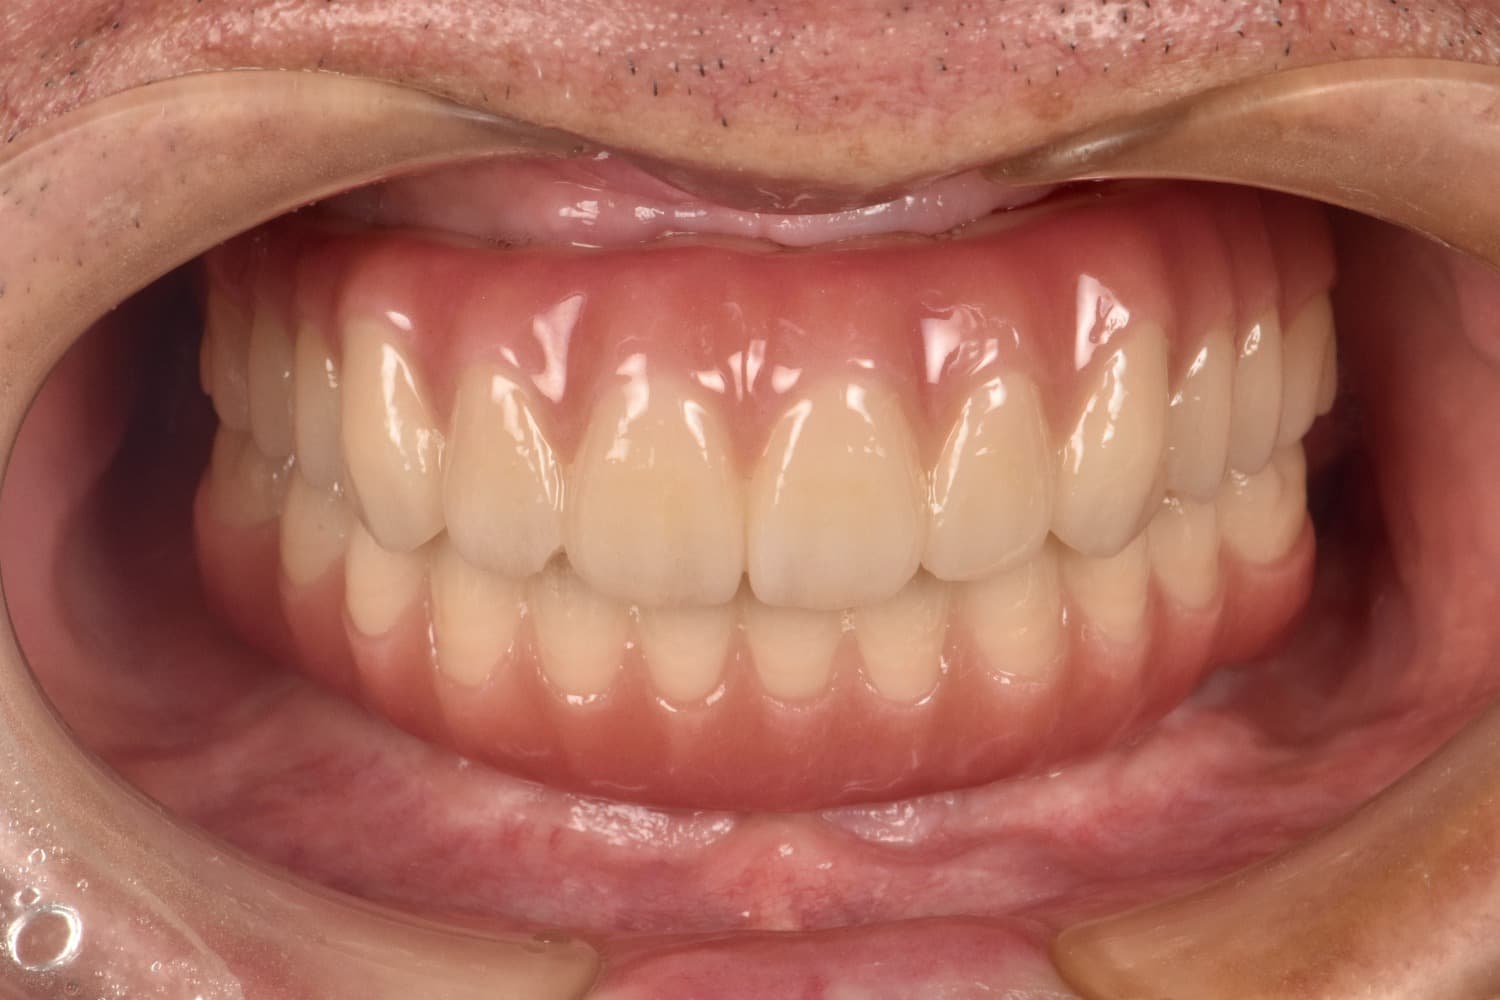

Before

重度の歯周病で上下すべての歯を抜歯せざるを得なくなった患者さまに対して、上下顎オールオン4で治療を行った。

年齢

70代

性別

男性

主訴

入れ歯が合わない 噛みにくい

治療期間

6カ月

治療回数

15回

費用

7,432,000円

副作用・リスク

清掃状態等により将来炎症を起こす可能性があります。